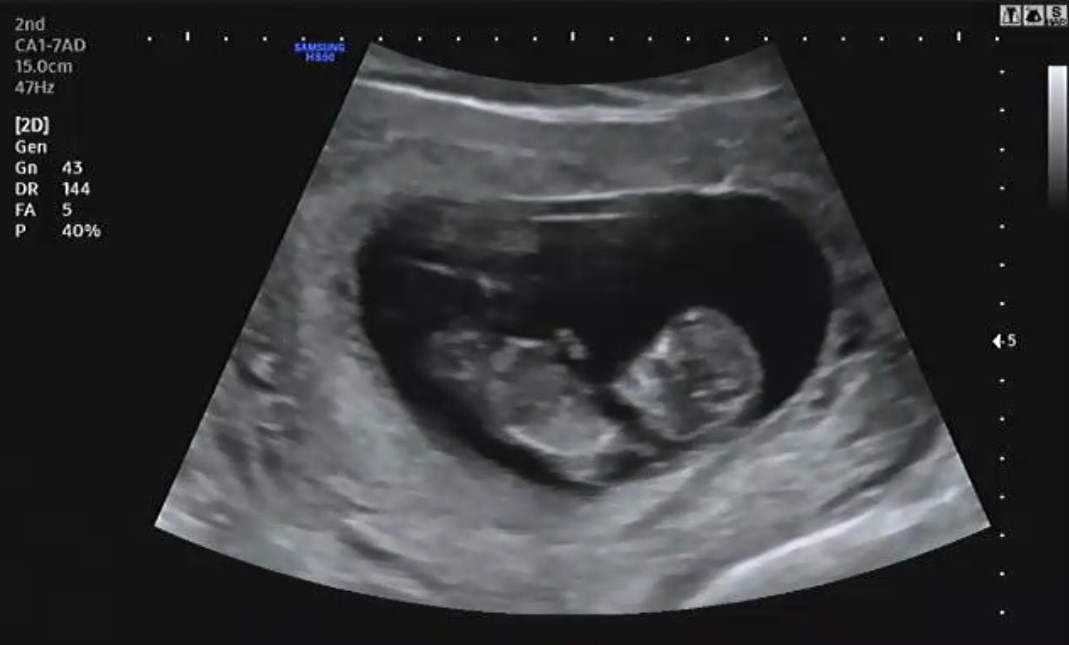

Screenshot_20190423-100836~01.jpg 임신 11주 1일 차

임신 초기에는 정확한 주수를 판별하기 어려운데 일반적으로 머리부터 엉덩이까지 길이를 측정해 임신 주수를 확인한다. CRL(머리부터 엉덩이까지 길이)의 측정을 통해 임신 초기가 끝나갈 때쯤 정확하게 임신 주수를 알 수 있다. 나는 이전 초음파에 비해 6일 정도 빨라 10주 2일 차가 아닌 11주 1일 차였다.

4주 만에 보는 햇님(태명)이는 젤리 곰 형태에서 사람의 형태로 바뀌었다. 완전한 사람의 형태는 아니지만 이제는 정말 내가 아기를 품에 안고 있다는 생각이 들었다. 한 달 만에 보는 아기는 제법 성장해서 얼굴에 눈코입 윤곽이 보이는데 너무나 신기했다. 나에게는 고작 4주였지만 아기에게는 엄청난 성장을 보여주는 기간이 되었다. 젤리 곰 마냥 짧고 동그랗게만 보이던 팔다리는 어느새 길어져 이리저리 휘젓고 있는 아기를 보니 또 감동을 받았다.

동그랗고 작지만 힘차게 뛰는 아기의 심장을 보며 마치 "여기서 엄마 곁에 있을게요." 하는 것처럼 느껴졌다.